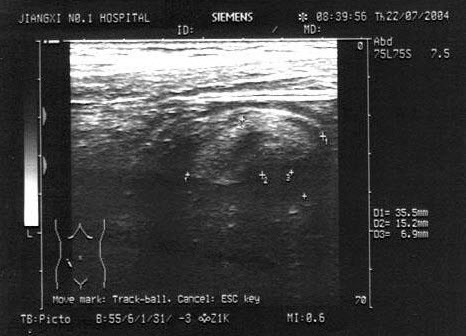

16、单项选择题

男,63岁,因左侧腰部疼痛不适伴无痛血尿1月余就诊,B超显示左肾集合系统分离3.9cm,如图所示,最可能的诊断为()

A.左输尿管结石

B.左输尿管癌

C.左输尿管炎性狭窄

D.左输尿管畸形

E.左输尿管血块